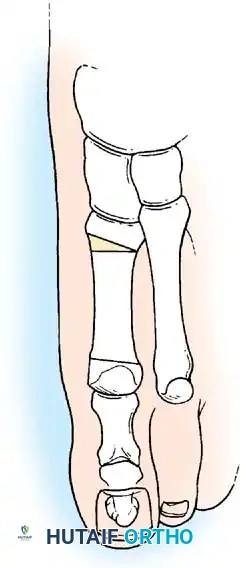

Hallux valgus (lateral deviation of the great toe) is not a single disorder, as the name implies, but a complex deformity of the fi rst ray that frequently is accompanied by deformity and symptoms in the lesser toes (Fig. 78-1). Often the angle between the fi rst and second metatarsals is more than the 8 to 9 degrees usually considered to be the upper limits of normal. The valgus angle of the fi rst metatarsophalangeal joint also is more than the 15 to 20 degrees considered to be the upper limits of normal (Fig. 78-2). If the valgus angle of the fi rst metatarsophalangeal joint exceeds 30 to 35 degrees, pronation of the great toe usually results. With this abnormal rotation, the abductor hallucis, which is normally plantar to the fl exion-extension axis of the fi rst metatarsophalangeal joint, moves further plantarward (Fig. 78-3). In this case, the only restraining medial structure is the medial capsular ligament with its capsulosesamoid portion (inserting into the base of the proximal phalanx) (Fig. 78-4) and capsulophalangeal portion (inserting into the plantar plate). The adductor hallucis, which is unopposed by the abductor hallucis, pulls the great toe further into valgus, stretching the medial capsular ligament (particularly the capsulosesamoid), attenuating this structure, and allowing the metatarsal head to drift medially from the sesamoids. In addition, the fl exor hallucis brevis, fl exor hallucis longus, adductor hallucis, and extensor hallucis longus increase the valgus moment at the metatarsophalangeal joint, further deforming the fi rst ray. The deep transverse intermetatarsal ligament runs between the plantar plates at the metatarsophalangeal joints and does not insert into bone on the adjacent sides of the metatarsal heads. Finally, the sesamoid ridge on the plantar surface of the fi rst metatarsal head (the crista) fl attens because of pressure (abutment) from the tibial sesamoid (Fig. 78-5). With this restraint lost, the fi bular sesamoid displaces partially or completely into the fi rst intermetatarsal space (see Fig. 78-2). In this situation, the patient is bearing less weight on the fi rst ray and more on the lesser metatarsal heads, increasing the likelihood of transfer metatarsalgia, callosities, and stress fracture of a lesser metatarsal.

a congruent metatarsophalangeal articulation; phalangeal osteotomy or distal metatarsal osteotomy, rather than tightening of the medial capsular repair, should be used for further correction. The valgus posture of the great toe frequently causes a hammer toe–like deformity of the second toe (Fig. 78-7). In addition, the splaying of the forefoot makes the wearing of shoes more diffi cult; with shoes that have a narrow toe box, corns often develop, as does bursal hypertrophy over the medial eminence of the fi rst metatarsal head (bunion). With valgus subluxation of the fi rst metatarsophalangeal joint, osteoarthritis frequently develops. In this case, the entire spectrum of hallux valgus is present: varus deformity of the fi rst metatarsal, valgus of the great toe, bunion formation, arthritis of the fi rst metatarsophalangeal joint, hammer toe of one or more toes, corns, calluses, and meta-